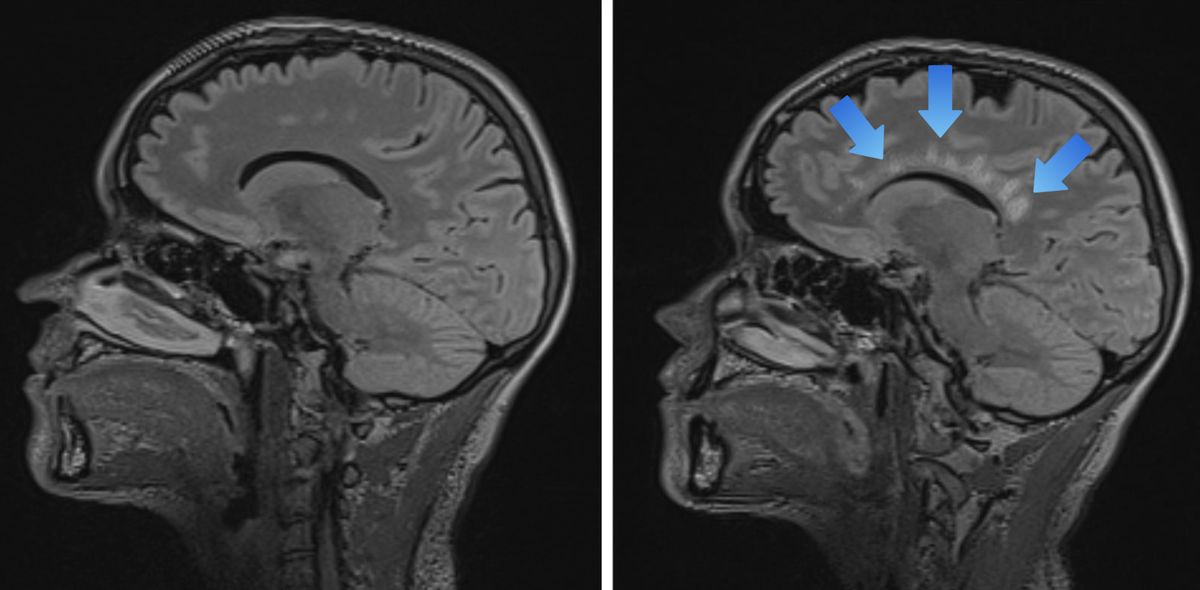

Pro diagnostiku RS je zcela klíčové vyšetření magnetickou rezonancí (MR), které jedinečným způsobem zobrazuje typická ložiska, jak je vidět na snímku vpravo níže (foto skutečného ložiska v mozku případně na mém Instagramu):

Vlevo normální nález, vpravo označují šipky typická ložiska, označovaná jako „Dawsonovy prsty“ (světlá místa).